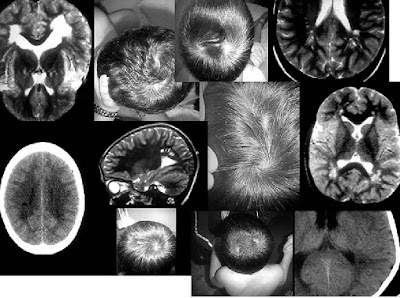

Recuerdo que de niño encontré en un libro de la biblioteca de mi abuelo Juan un capítulo dedicado a las corrientes y remolinos de nuestro pelo con gran profusión de fotografías, en blanco y negro, claro, en que unas flechas rojas indicaban la dirección de esas corrientes. Algo parecido a los mapas de isobaras que nos explican después de los telediarios. Sin embargo no recuerdo nada sobre lo que se decía sobre ello, bien porque no era dado a la lectura o simplemente porque el libro estuviera escrito en inglés, francés o alemán.

Es un tema para mí interesante y recurrentemente aparecen en mi cerebro aquellas imágenes llenas de flechas rojas sobre todo el cuerpo de individuos peludos. Varias veces he buscado en lo poco que conservo de aquella fastuosa biblioteca sin obtener resultados. Y muchas más he buscado en Internet, encontrando muchas páginas de belleza personal, donde se interpretan los remolinos cono un problema de peinado, y muy pocas de caracter científico.

Los científicos dicen que no sólo ocurre en los humanos, sino también en animales, desde la fase embrionaria. El ectodermo primitivo es el origen común del sistema nervioso, la piel y sus anejos. Las rotaciones capilares son definidas por genes que indican la dirección de crecimiento de los cabellos; ya sea para frente, para atrás o para un lado. De hecho, existen estudios sobre la correlación entre la creación de remolinos y la dirección del crecimiento del pelo y la tensión en la epidermis en el momento en que se forman los folículos pilosos (con una comparativa de patrones de remolinos en fetos normales y en fetos malformados a la que no hemos tenido acceso).

Según los estudios del genetista Amae Klar, existe una clara conexión entre la dirección de nuestros remolinos capilares y que seamos diestros o zurdos. Al menos el 90% de los diestros tenían remolinos que giraban en la dirección de las agujas del reloj, mientras que sólo un 10% contaba con la tendencia contraria. De hecho, descubrió que posiblemente de la misma forma que la genética determina que seamos diestros o zurdos, también determinará la dirección de nuestros remolinos, ya que un 50% de las personas zurdas o ambidiestras tenían remolinos en la dirección contraria a las agujas del reloj. Y es que cuando el feto se va formando, el cerebro se forma al mismo tiempo que la piel y el pelo, y tanto el cuero cabelludo como el espacio de la membrana del cerebro proceden de la misma estructura embriológica.

También existen casos de dos remolinos, uno en sentido de las agujas del reloj y el otro va en sentido contrario. Esto en el área de la coronilla, pues el cuello y el flequillo son también áreas de turbulencias. En general pueden aparecer en cualquier área en que haya pelo.

El caso de doble remolino se ha estudiado científicamente como una alteración de las estructuras ante agresiones producidas durante la embriogénesis sobre la lámina ectodérmica. Hasta el momento actual se han descrito múltiples asociaciones neurocutáneas, algunas de ellas catalogadas como síndromes o enfermedades, la mayoría determinadas genéticamente. En la revista digital de neurología neurología.com se plantean varios casos clínicos: Cinco pacientes varones con edades comprendidas entre 2 y 7 años, en los que encontraron un patrón común de desviación del desarrollo psicomotor y conductual consistente en un trastorno de hiperactividad e impulsividad asociado a un retraso en la adquisición del lenguaje. Todos ellos tenían en común tanto la implantación del cabello en doble remolino, como la dilatación de los espacios de Virchow-Robin (en las fotos junto a los dobles remolinos) en el estudio de neuroimagen.

Otros piensan que el gen encargado de la orientación capilar parece tener la capacidad de eliminar ciertos tipos de cáncer, por lo que poseer un remolino en el pelo puede acabar siendo una auténtica ventaja evolutiva. Desde que el gran biólogo español Antonio García Bullido y su pupilo británico, David Gubb, desentrañaron el código genético de la mosca del vinagre, se descubrió que los genes de polaridad son una especie de brújula para las células de nuestro cuerpo, ya que son los encargados de organizar la orientación del crecimiento de los tejidos. Los genes de polaridad son útiles para una variedad de cosas diferentes en el cuerpo humano. Ayudan en el flujo y la distribución de nutrientes entre las células, así como dictan dónde se encuentran la parte delantera y trasera de las células. En resumen, los genes de polaridad son vitales para la correcta operación celular. Sin embargo, un efecto secundario de estos genes de polaridad es la tendencia de las estructuras corporales a crecer en patrones opuestos, lo que conduce a cosas como los mechones. Entre otras cosas, se cree los genes de polaridad son responsables del crecimiento de los remolinos en el pelo, y la predominancia de un hemisferio cerebral sobre el otro (ser diestro o zurdo). El caso de doble remolino se ha estudiado científicamente como una alteración de las estructuras ante agresiones producidas durante la embriogénesis sobre la lámina ectodérmica. Hasta el momento actual se han descrito múltiples asociaciones neurocutáneas, algunas de ellas catalogadas como síndromes o enfermedades, la mayoría determinadas genéticamente. En la revista digital de neurología neurología.com se plantean varios casos clínicos: Cinco pacientes varones con edades comprendidas entre 2 y 7 años, en los que encontraron un patrón común de desviación del desarrollo psicomotor y conductual consistente en un trastorno de hiperactividad e impulsividad asociado a un retraso en la adquisición del lenguaje. Todos ellos tenían en común tanto la implantación del cabello en doble remolino, como la dilatación de los espacios de Virchow-Robin (en las fotos junto a los dobles remolinos) en el estudio de neuroimagen.

Ahora, investigadores de la Universidad Estatal de Michigan también han descubierto que la proteína responsable de su manifestación es capaz de impedir la formación de ciertos tipos de tumores, como el retinoblastoma. Lo que significa que tener remolinos es un indicador de que esta proteína se encuentra presente en nuestro cuerpo, lo que nos hace menos propensos a sufrir retinoblastomas. Los investigadores de MSU llegaron a esta conclusión experimentando con moscas de la fruta. Cuando eliminaron la proteína de las moscas, descubrieron que su cabello perdió cualquier señal de remolinos (fotos de la derecha), lo que les hizo creer que la misma proteína que gobierna los genes de la polaridad también puede ser responsable de ellos. De ser así, los científicos podrían desarrollar un nuevo tipo de quimioterapia que se centre en restaurar esta proteína en los pacientes.